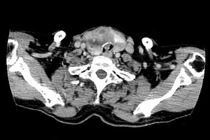

Các bác sĩ khoa Ung bướu vừa phẫu thuật nội soi bằng đường miệng thành công cho bệnh nhân Đ.T.T.T (42 tuổi) ở phường Cửa Ông, tỉnh Quảng Ninh. Bệnh nhân đi khám sức khỏe tổng quát, siêu âm phát hiện thuỳ trái tuyến giáp có khối u kích thước 4x5mm.

Chọc tế bào chẩn đoán ung thư thùy trái tuyến giáp và chỉ định điều trị bằng phương pháp phẫu thuật nội soi qua đường miệng cắt thùy trái và eo tuyến giáp kèm nạo vét hạch cổ trung tâm.